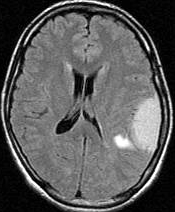

左は,造影剤を使ったガドリニウム増強MRIです。腫瘍が白く丸く見えます。右はフレア画像で,腫瘍の周囲の脳浮腫(脳のはれ)です。左前頭葉が,かなり強くはれています。この腫瘍は小さいのですが,脳のはれが強すぎるので手術摘出したほうがいいです。浮腫が悪化すると,てんかん発作や認知機能低下がでる可能性があります。

MRIでの髄膜腫の見え方は撮影の仕方によっていろいろです。左からT1強調画像,T2強調画像,フレア画像といいます。腫瘍の横に小さく白い領域がありますが,これは脳の腫れた部分で脳浮腫といいます。髄膜腫があると周囲に脳浮腫が生じることがあります。

最も見やすいのが,ガドリニウム造影剤を注射して撮影するものです。一般的に髄膜腫は造影剤で白く映し出されます。この腫瘍は左脳側にあります。MRIの軸面という輪切りの写真では左右が逆になりますから注意してください。脳を下から見た図になっています。MRIはいろいろな方向から腫瘍を見ることができますが,右は冠状断という正面から見た図です。よく見ると腫瘍の上と下のはじっこに線状に糸を引いたように造影される部分があります。これをテールサイン(しっぽのサイン)といいます。腫瘍が硬膜に沿って延びている可能性があることを示しています。